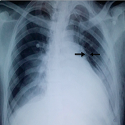

Hyperparathyroidism related to an ectopic parathyroid adenoma

Attifi Hicham, Messary Abdelhamid

PAMJ. 2014; 19: 135. Published 08 October 2014